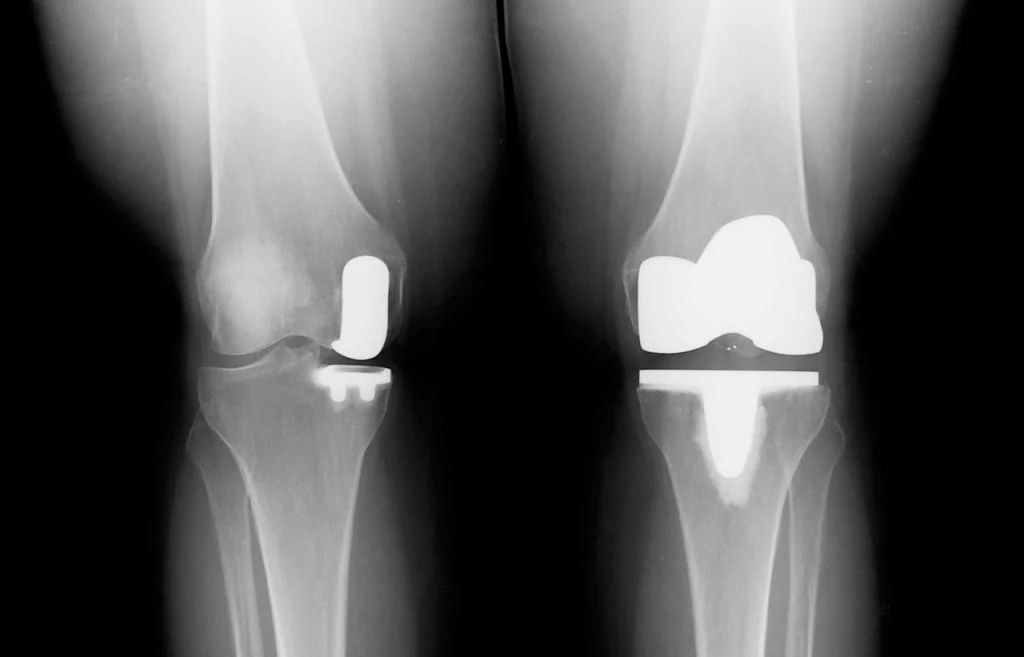

Отличия от тотального эндопротезирования

Длительное время ТЭКС (тотальное протезирование коленного сустава) признавался ведущим методом при лечении остеоартроза. Какие же преимущества имеет одномыщелковое эндопротезирование:

- Гораздо меньший объем хирургического вмешательства;

- Быстрый восстановительный период (уже через несколько месяцев пациент может возвращаться к своим повседневным физическим нагрузкам);

- Менее выражен болевой синдром (как в покое, так и при интенсивной физической нагрузке);

- После частичного эндопротезирования люди вдвое реже жалуются на трудности при использовании автомобиля, чем после тотального;

- Вдвое меньше случаев ограничения сгибания в коленном суставе и контрактур;

- Гораздо чаще людям с частичным эндопротезом доступно положение сидя на корточках, посадка и выход из автотранспорта, наклон и подъем предметов с пола, бег.

Целый ряд неоспоримых и важных преимуществ однополюсного протезирования. Большинство зарубежных коллег подчеркивают у себя схожесть приведенных результатов.

Сравнение двух типов операций.

Перелом со смещением требует вправления и фиксации мыщелков металлическим болтом. В тех случаях, когда не представляется возможным восстановить нормальную суставную поверхность, мыщелок заменяется эндопротезом.